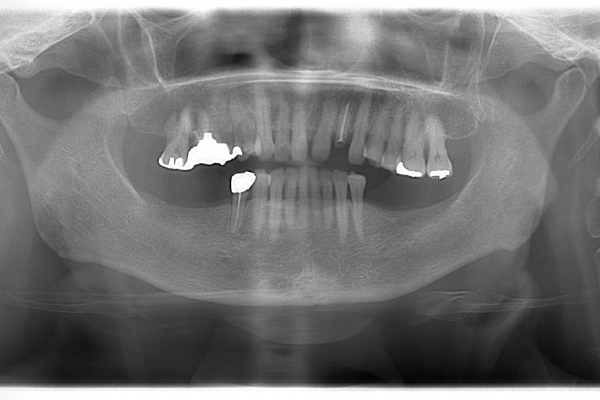

| 年齢 | 50代男性 |

|---|---|

| 主訴 | 全体的にチェックしたい |

| 治療方針 | 全体的に10年以上前の治療痕で、銀歯の下でカリエスになっています。今回は右上5に限っての方針を記載する。 |

| 治療期間 | 4ヶ月 |

| 費用 | ・MTM 110,000円 ・ファイバーコア 16,500円 ・セラミッククラウン 110,000円 |

※全て税込となります。

カリエスを取り除くと、遠心の歯質が歯肉縁下になりました。

左上2は広範囲にわたってCRが充填されているのがわかります。またその周囲に透過像があり、カリエスになっていることもわかります。